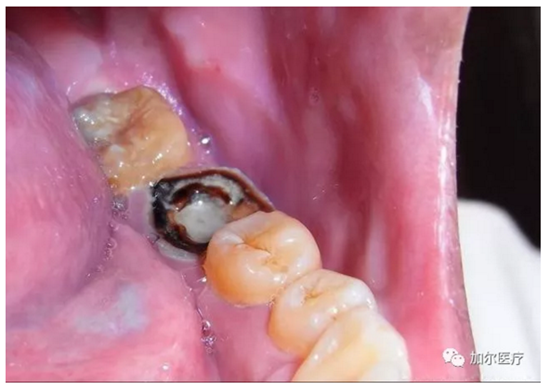

蛀牙連一半的牙冠都沒了,但是牙齒又不疼,而且還有些發(fā)黑,牙醫(yī)拍片檢查后才知道得做根管治療,那時牙痛真要人命,可是怎么判斷牙髓壞死?

1.png

簡單來說,可以看牙齒表象!觀察顏色是否變黑變暗,實際上這顆牙齒和死牙沒什么區(qū)別,不過比任何假牙好太多了,牙冠再怎么殘缺是一回事,關(guān)鍵自帶天然牙根,只要修復(fù)好和真牙咀嚼功能還是一樣,要不然怎能讓你輕易拔牙呢?